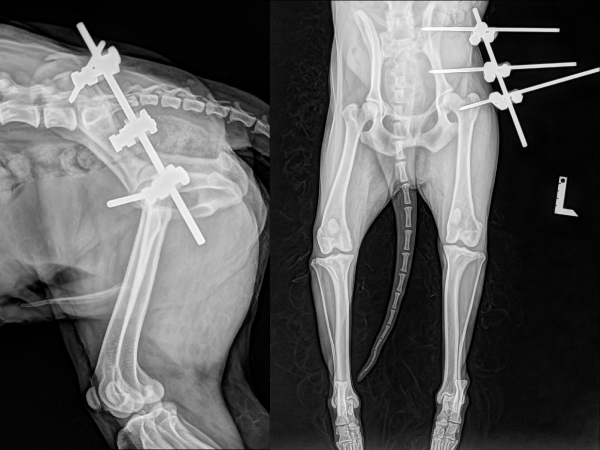

<創外固定後のレントゲン>

創外固定による固定を行いました。大腿骨が寛骨臼の定位置に整復されています。数週間固定を維持し、関節包の繊維化による安定化を図ります。

<創外固定抜去後約1か月のレントゲン>

再脱臼することなく、大腿骨頭が寛骨臼の定位置に安定しています。